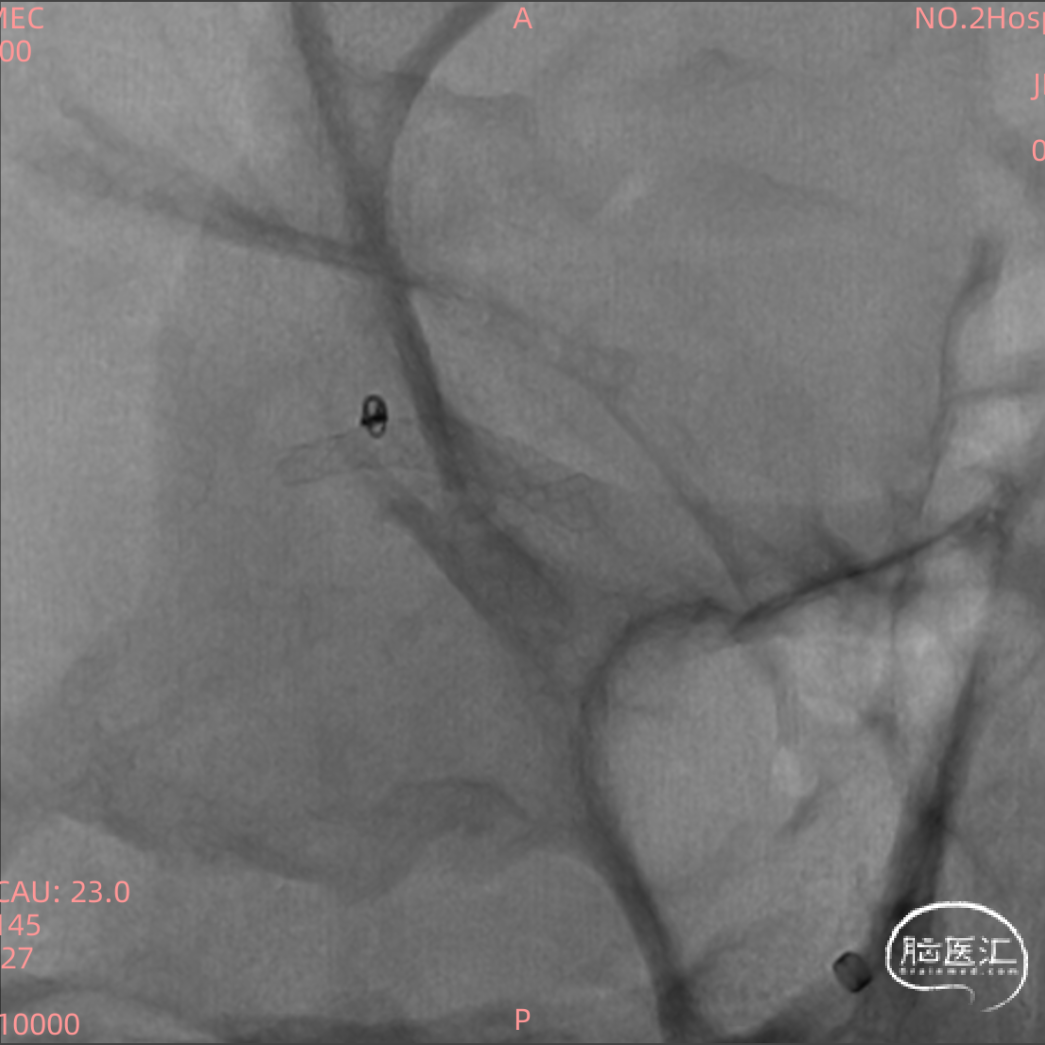

术前头部CT:

根据造影结合患者头部CT出血分布考虑朝上方的较大动脉瘤(1.3mm*1.2mm)为破裂出血的责任动脉瘤,但是其瘤体小难以致密填塞,并且朝下的微小动脉瘤约0.8mm,难以进行弹簧圈填塞,故考虑破裂动脉瘤予以1枚弹簧圈疏松填塞加快瘤内血栓形成后置入密网支架覆盖上下两枚动脉瘤进行血管壁修复。

支架选择:

测量血管远端1.5mm,近端2.5mm,支架直径选择3.25mm,因为该部位有豆纹动脉发出,故考虑选择一枚短支架(15mm),尾端置于大脑中动脉M1段远端1/3。

超选破裂约1mm微小动脉瘤:

直接将导丝放入微小破裂动脉瘤内超选微导管风险极高,故将SL-10导管头端进行“S”塑形后,将SL-10导管先置于动脉瘤远端血管后再回拉弹入动脉瘤内填塞1mm*2mm(Target)弹簧圈。

远端释放技术:

系统在M2段退管,支架打开约5mm后回拖,通过轻推回拉使支架缓慢释放,非常顺畅。

中段释放技术:

远端释放支架后,保持XT-27位于血管中间位置,为更好贴壁,轻推系统,中段缓慢释放。

近端释放技术:

轻推后卸张力,保持微导管居中,撤微导管,支架完全打开,XT-27跟进。

根据造影结合患者头部CT出血分布考虑朝上方的较大动脉瘤(1.3mm*1.2mm)为破裂出血的责任动脉瘤,但是其瘤体小难以致密填塞,并且朝下的微小动脉瘤约0.8mm,难以进行弹簧圈填塞,故考虑破裂动脉瘤予以1枚弹簧圈疏松填塞加快瘤内血栓形成后置入密网支架覆盖上下两枚动脉瘤进行血管壁修复。

大脑中动脉多发微小动脉瘤,并且微小动脉瘤破裂相对少见,Surpass Evolve支架的释放及贴壁非常丝滑,操作简单,此病例难度在于微小破裂动脉瘤的弹簧圈填塞,并且支架释放过程中对微导管的影响较小。